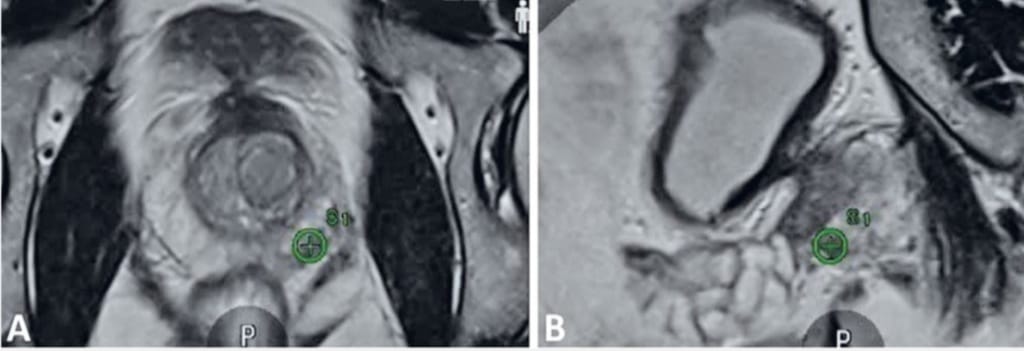

Biopsia RMN-fusion combină imagistica prin rezonanță magnetică multiparametrică (IRM/mp) cu ghidarea ecografică transrectală, permițând medicului să identifice și să preleveze țesut exact din zonele suspecte identificate ale prostatei. Astfel, precizia diagnosticului crește semnificativ comparativ cu biopsiile clasice realizate „în orb”.

Principiul procedurii se bazează pe suprapunerea imaginilor obținute anterior prin RMN peste imaginile ecografice în timp real. Software-ul dedicat fuzionează cele două seturi de date, generând o hartă tridimensională detaliată a prostatei. Această abordare permite prelevarea țintită a probelor din leziunile cu risc crescut, identificate anterior prin RMN ca fiind suspecte conform scorului PIRADS.